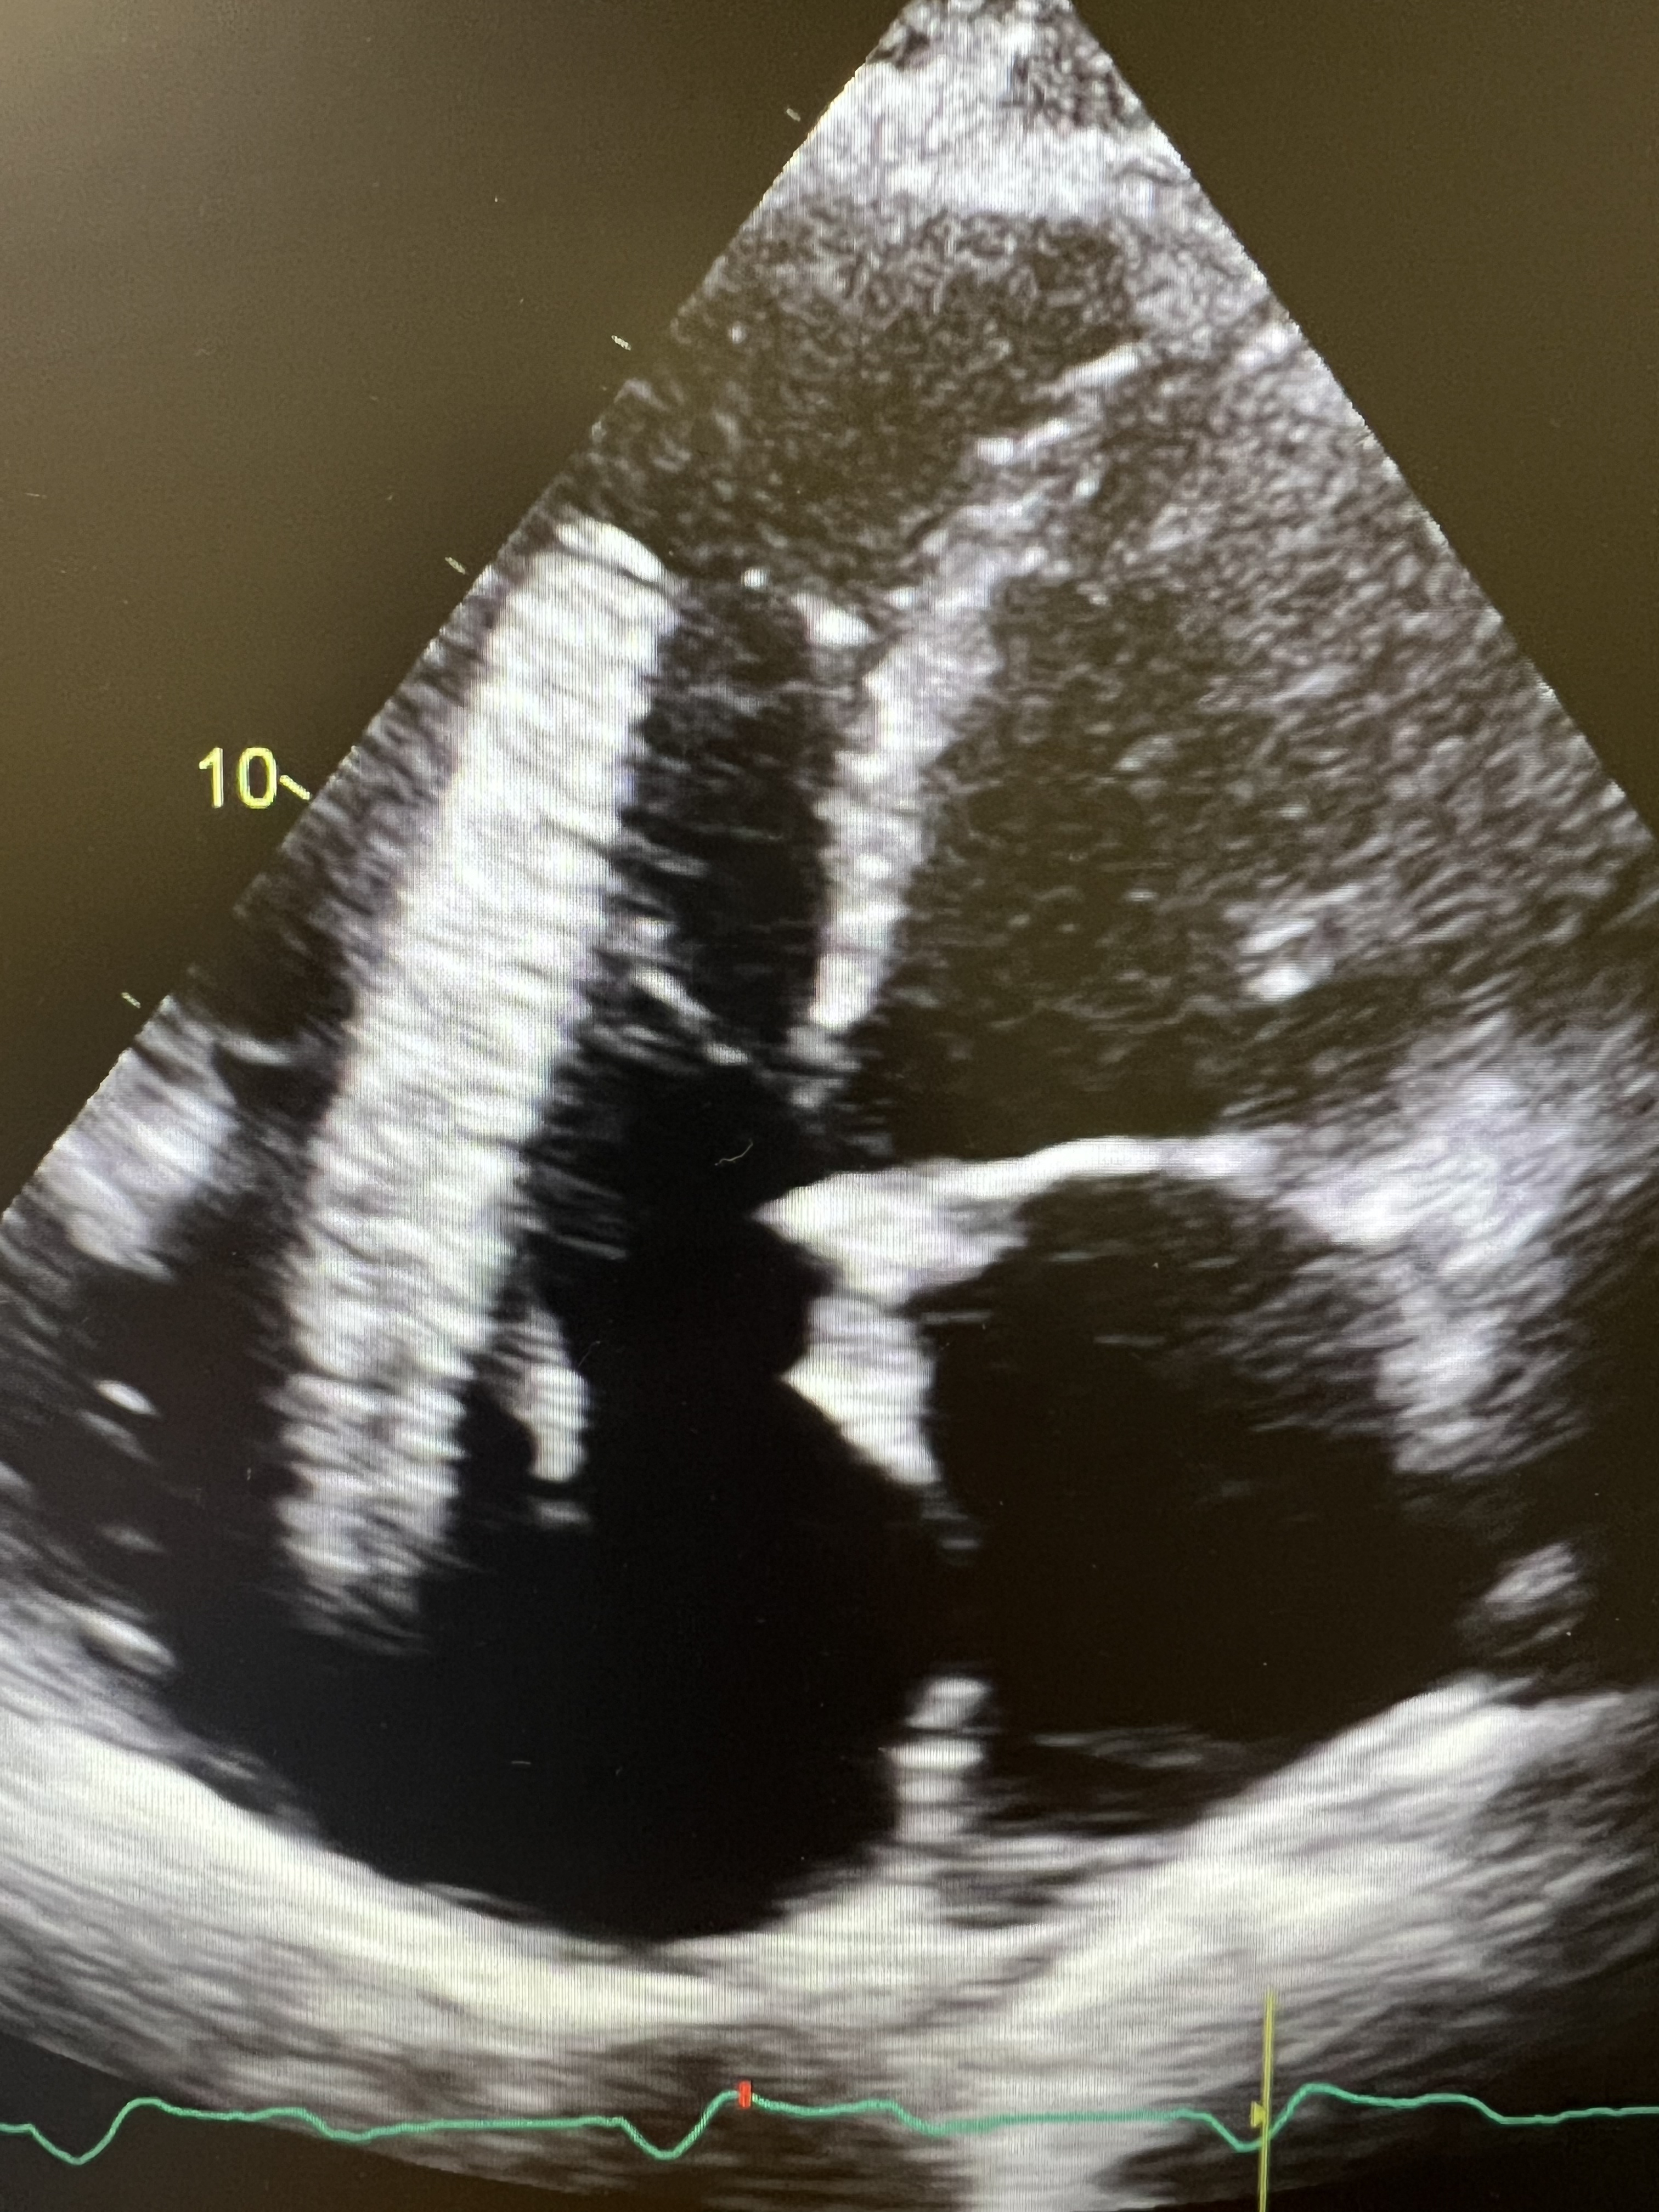

A 69-year-old male with extensive cardiac and peripheral vascular disease. Presented to our clinic with episodes of dizziness, dyspnea, and chest pain. Episodes occur during the day, relieved with rest. Examination was significant for systolic murmur, healed foot ulcer, moderate lower extremity swelling, and varicose veins. Patient has received a (16 x 100 Zilver venous stent) for severe stenosis in the left iliac vein in 3/2022. Transthoracic echocardiography showed an echodense tubular structure measuring 10 x 2 centimeters, resembling a stent, in the right atrium crossing the tricuspid valve into the right ventricle and holding the tricuspid valve open, causing severe TR. Cardiac catheterization was performed, confirming the stent position. The patient underwent surgical extraction of the stent and tricuspid valve repair.